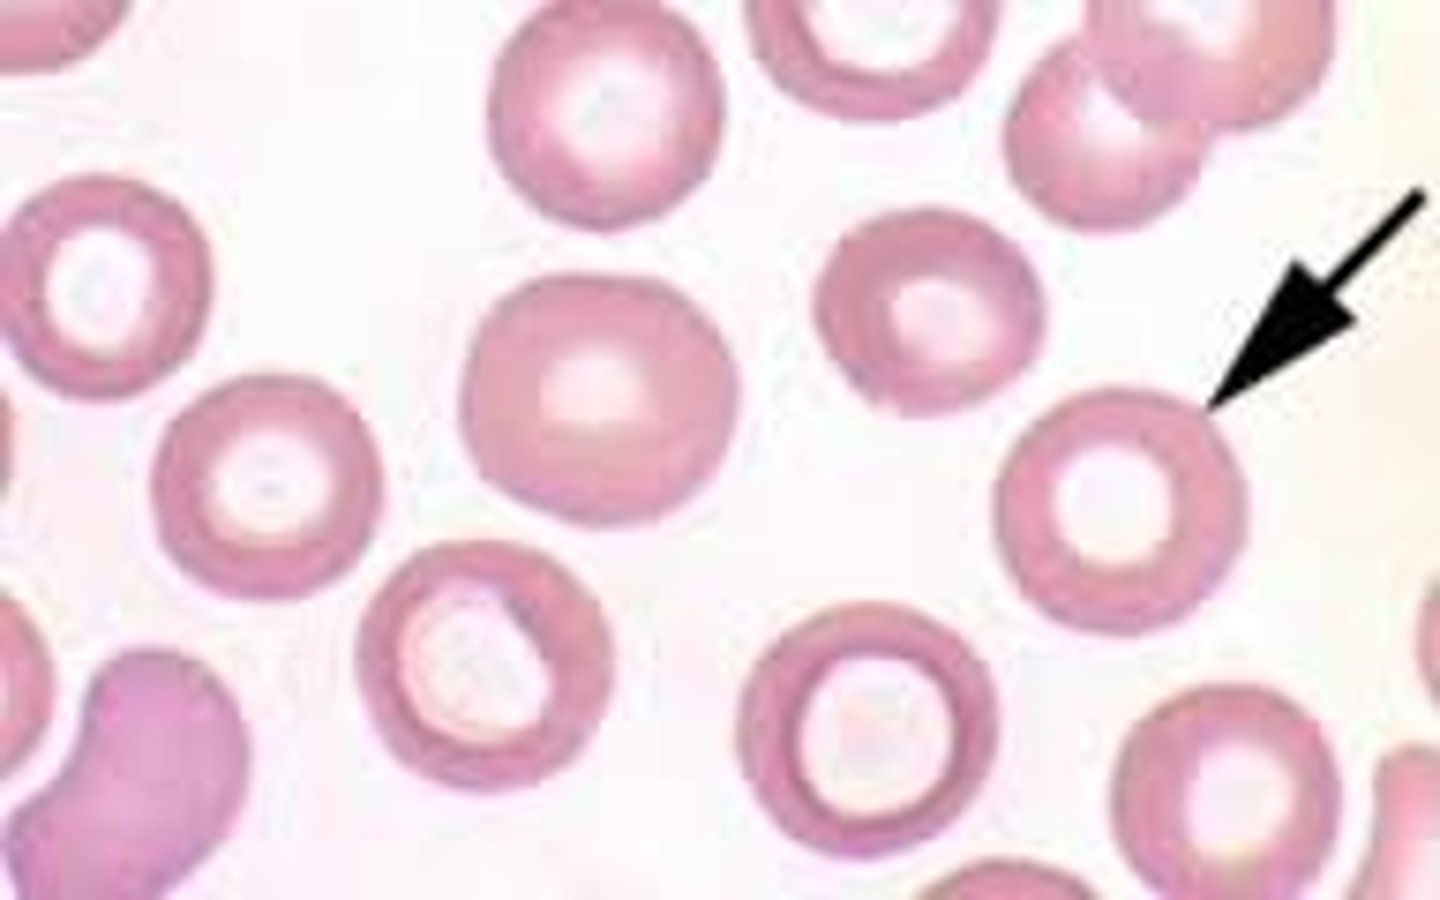

target cells

hypochromasia

increased level of central pallor

-decrease hemoglobin concentration

torocytes

AKA punched out cells

- "donut" hole presentation

--artifact